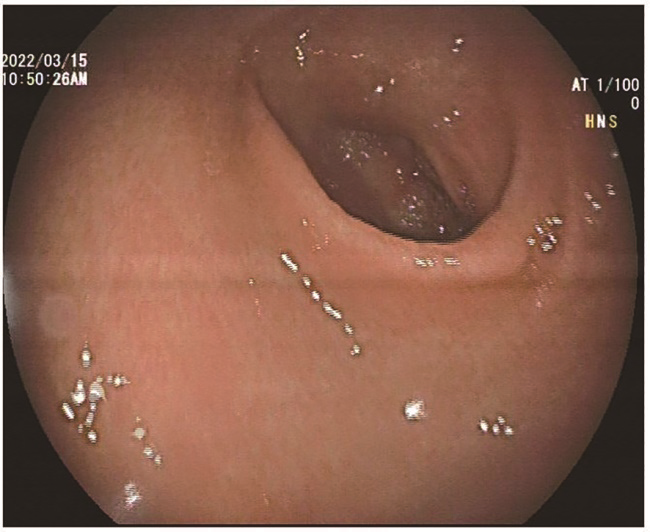

GVHD的发生及演变(图2):HSCT后28 d,患者出现纳差,肝功能总胆红素24.4 μmol/L,碱性磷酸酶355 U/L,谷丙转氨酶116 U/L,考虑急性GVHD肝损害(肝炎型),予调整CsA剂量(图1)联合MP免疫抑制等治疗后病情好转。HSCT后5个月MP、CsA完全停服,6个月患者再次出现纳差、黄疸,总胆红素最高升至57.3 μmol/L,查肝胆彩超未见肝肿大、胆道扩张及梗阻,不支持肝静脉闭塞性疾病,仍考虑急性GVHD肝损害,再次予强化免疫抑制治疗后好转。1年余患者出现口腔溃疡、皮肤疱疹,伴水肿、尿蛋白3+、血白蛋白23 g/L,血肌酐正常,考虑慢性GVHD累及口腔黏膜和皮肤、HSCT后肾病综合征,停用CsA,改为他克莫司,联合MP免疫抑制治疗后症状改善。3年余患者出现全身皮肤呈白癜风样改变,趾甲如病甲改变(图3)。4年余患者水肿、蛋白尿加重,血肌酐升至293 μmol/L,肾活检病理提示GVHD相关的膜性肾病、肾小管间质病变较重(不排除合并慢性肾小管间质性肾炎可能,图4),遂停用他克莫司,改为MMF联合MP免疫抑制治疗。同年血肌酐升至722 μmol/L,进入腹膜透析治疗。9年余患者气促,先后2次胸部CT提示单侧(右)胸腔中-大量积液,胸水检查排除感染及肿瘤,结合患者无右颈内静脉置管病史,无上腔静脉阻塞体征,考虑为GVHD浆膜积液可能,予引流等对症并加用MP治疗后胸腔积液未再复发。此外,HSCT后2年始患者反复出现腹痛、排血性水样便,每次均在予MP免疫抑制治疗后好转,考虑为急性GVHD胃肠道受累。近1年来患者再次发作性血性水样便(图5),胃管引流出血性液体,胃镜(图6)及全腹部CT平扫未见明确占位病变等(图7),不排除胃肠道GVHD症状,经抑酸、护胃等对症治疗后好转。自此截至2022年5月,患者未再使用糖皮质激素及免疫抑制剂,目前处于维持性血液透析、长生存状态。

注:胃镜下胃窦黏膜充血水肿,黏膜损伤